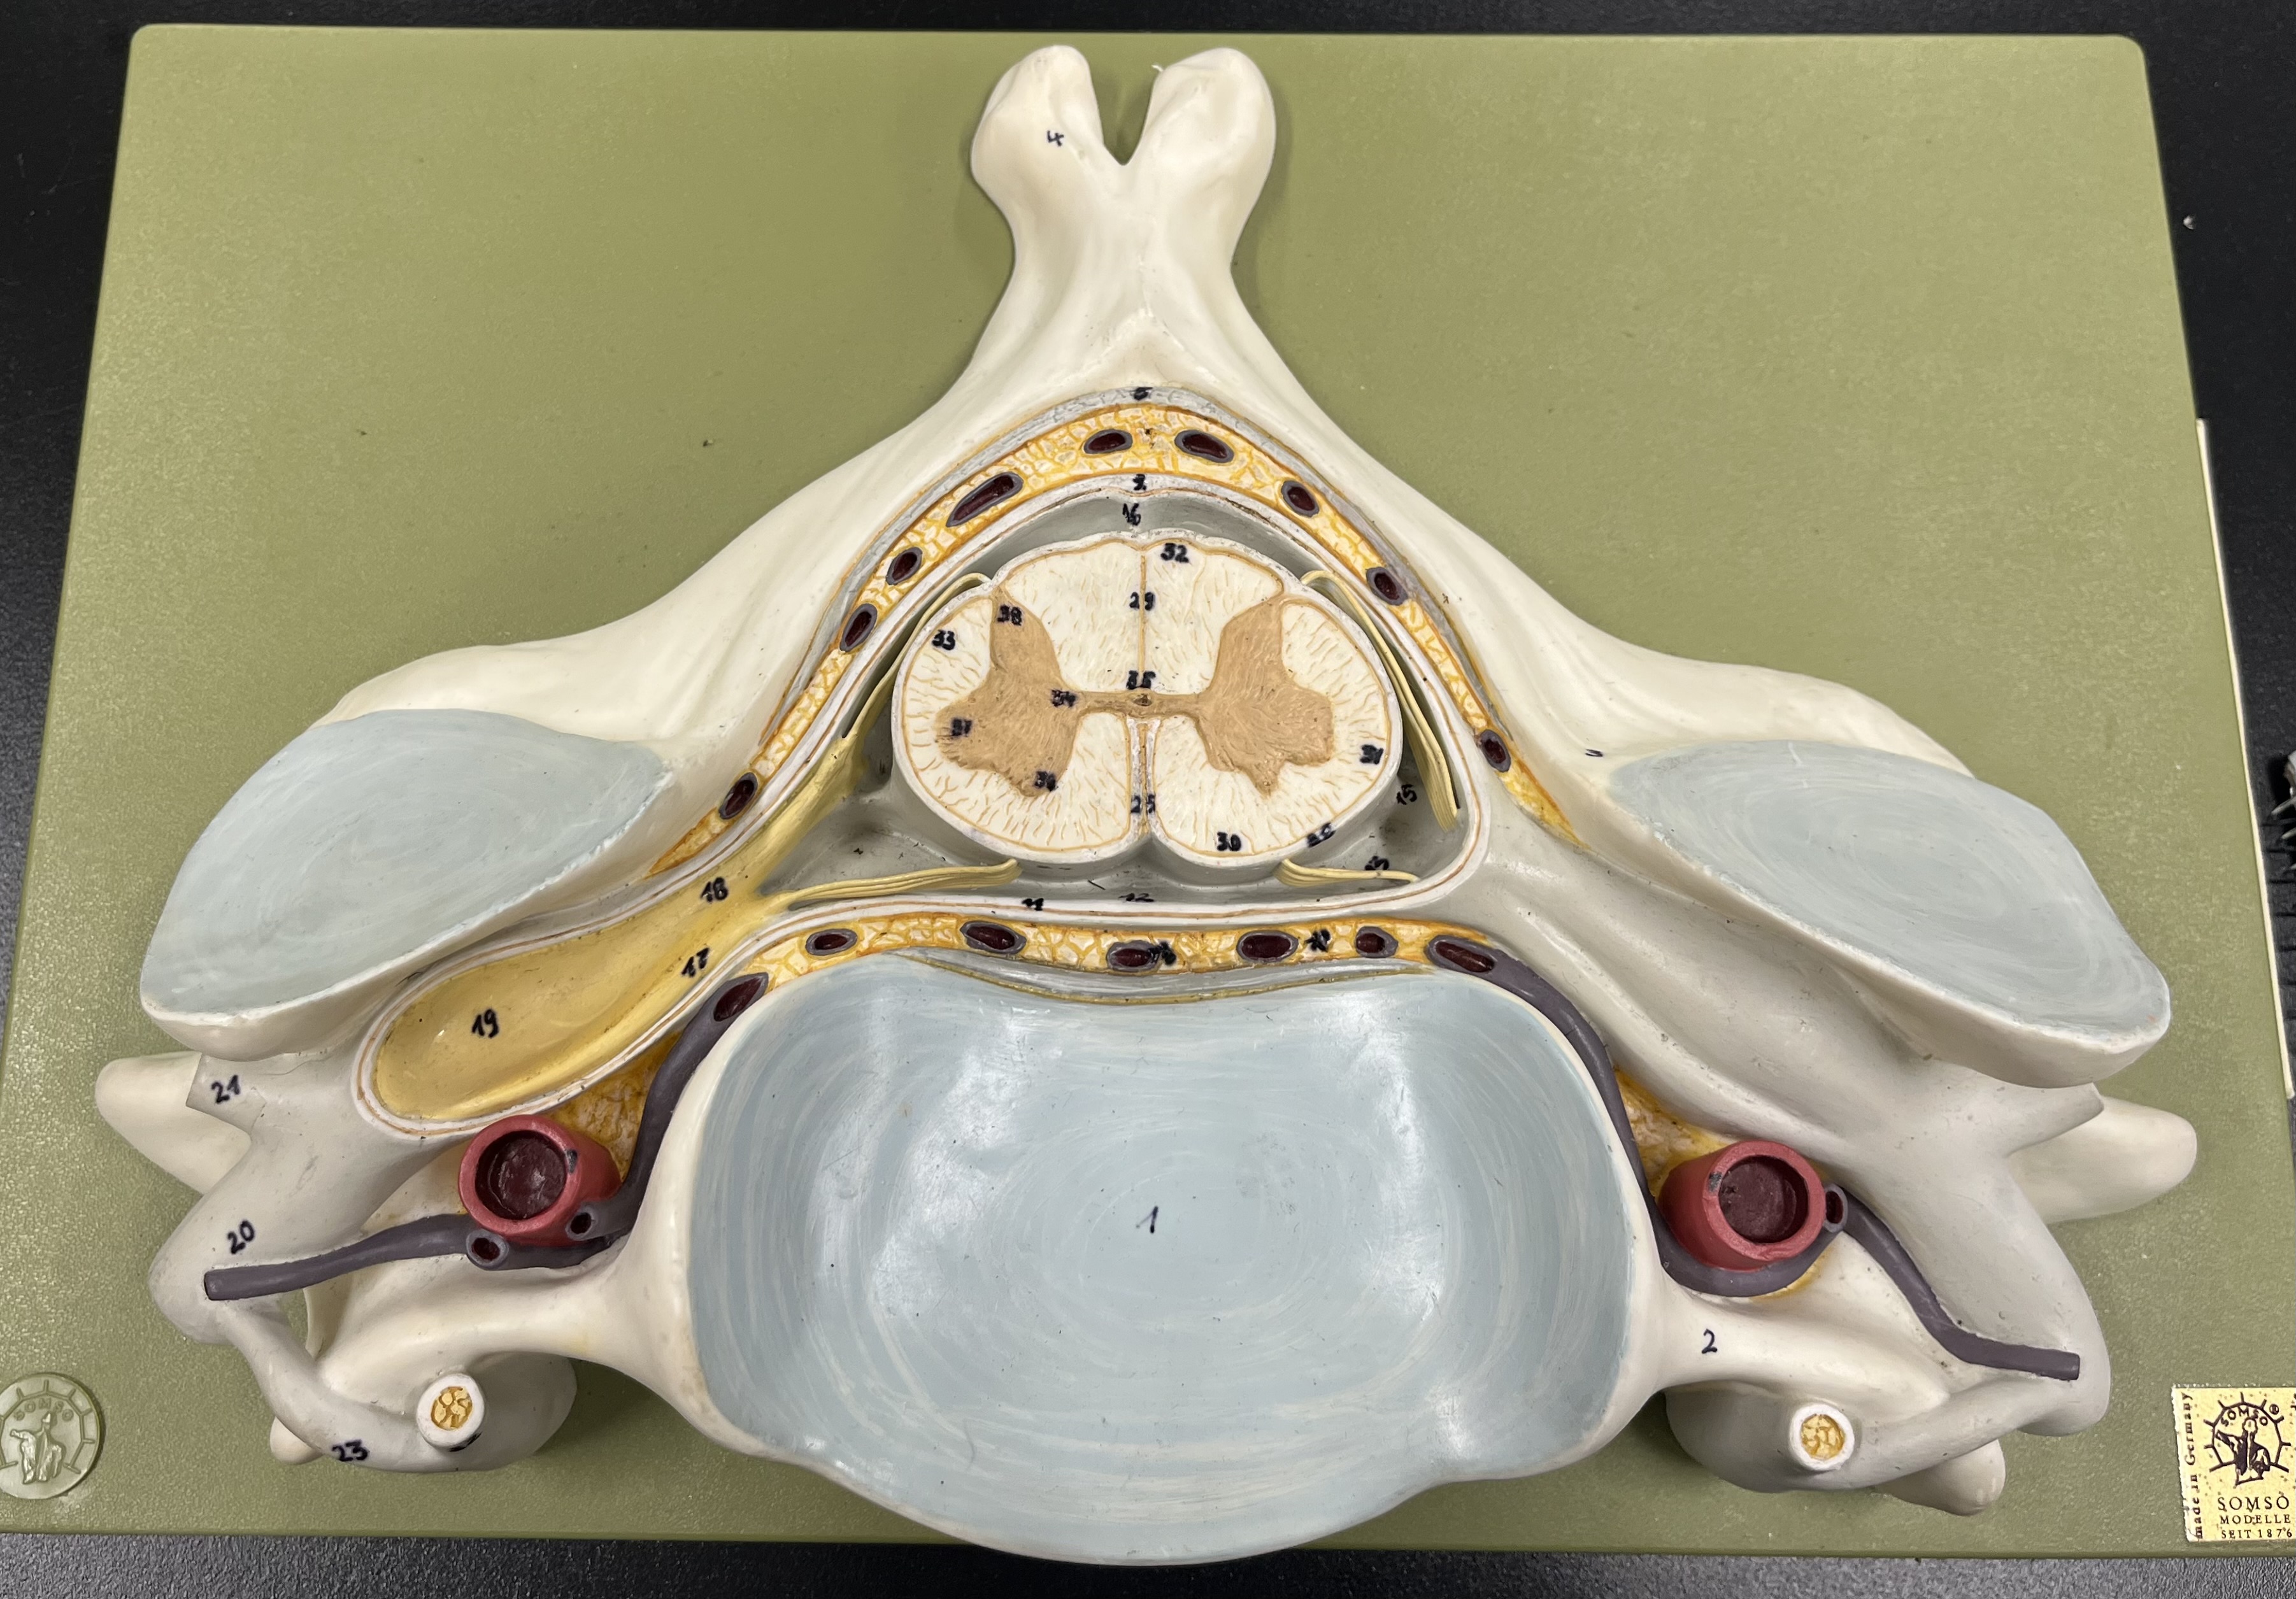

epidural space

dura mater

subdural space

arachnoid mater

subarachnoid space

pia mater

denticulate ligaments

What is the groove here?

anterior median fissure

posterior median sulcus

posterior (dorsal) horn

posterior (dorsal) horn; R—>L

anterior (ventral) horn

lateral horn (selected models)

gray commissure

central canal

anterior column

lateral column

posterior column

white commissure

posterior (dorsal) root ganglion

What is the bulb here?

posterior (dorsal) root ganglion

posterior (dorsal) root

posterior (dorsal) root

anterior (ventral) root

anterior (ventral) root

dorsal ramus

dorsal ramus

ventral ramus

ventral ramus

rami communicantes

rami communicantes

sympathetic chain ganglia

sympathetic chain ganglia